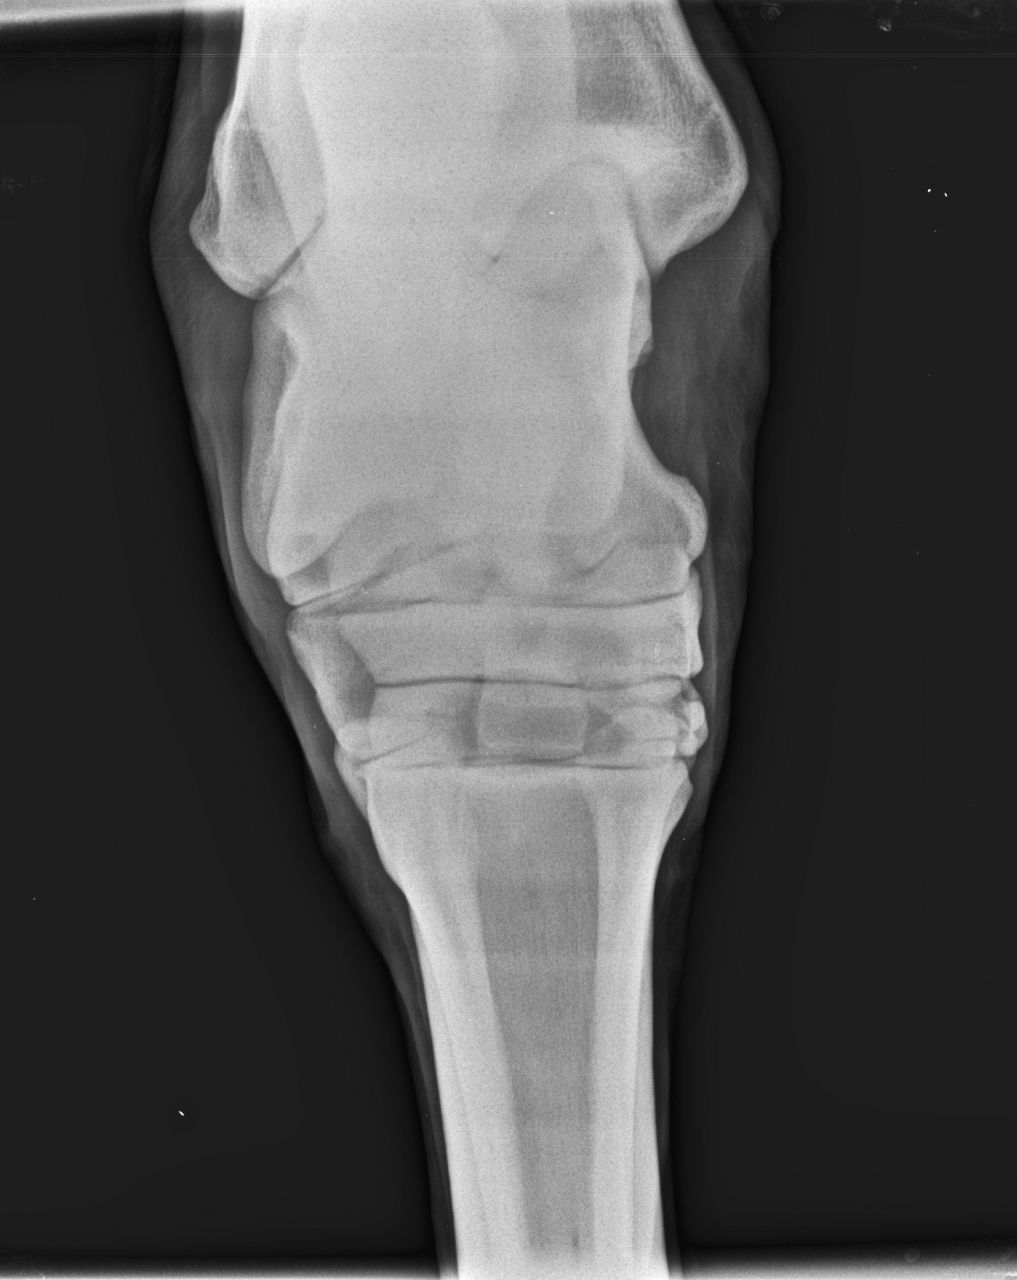

| Dire merci | donc, voilà ... ensuite, il recommence à travailler bien, on essaie quelques barres à nouveau et ça va pas mal du tout ... toujours pareil : franc, allant ... Mais je l'emmène chez le véto, je veux mon contrôle ... BIlan (je ne l'ai pas j'ai juste les radios) : sur le cercle bon à droite c'est pas top. On été fait aussi au passage une echo du grasset pour être certain qu'il n'y ai pas de soucis plus haut. Une anesthésie de je ne sais plus quel nerf, après laquelle ont été refait les tests de flexion et sur le cercle. Amélioration mais très légère et pas assez franche, donc radios du jarret. cheval "gêné" aux tests mais pas boiteux, toujours pareil. c'est pas franc. EPARVIN en formation (on voit à peine l'augmentation de la densité au niveau de l'interligne) mais cette année ON VOIT ! quelque chose de concret Halleluiah ! et en plus y'a autre chose, il demande un avis chir et va montrer les radios à son collègue et dois me rappeler. ... |

| Dire merci | une carrière pas top à un manège et carrière en sable de fontainbleau...et ba..rien à voir.. (le rêve tu m'étonnes) ça c'est certain ! le sol est important. J'ai eu la chance d'avoir toujours de bons sols sauf où je suis le manège est pas terrible. Du coup on se promène pour travailler en LP. Notre piste de galop n'est pas dégueu et on va y passer du temps je pense à marcher... Je suis assez partante pour le TILDREN d'emblée. Je me posais la question en été dernier déjà mais je suis assez contre la chimie quand rien n'est déclaré. Et rien n'était déclaré .... !! c'était mon SEUL soucis. du coup j'avais arrêté de sauter jusqu'en hiver. On a repris sur petit, ça allait bien. L'irrégularité était présente quand on a recommencé après un mois d'arrêt. Mon instructeur soupçonnait surtout un manque de muscle ou une raideur de "repos". Bon moi certains mouvement, en liberté me faisaient tiquer et je "sentais" que quelque chose n'allait pas mais c'était pas CLAIR. alors une petit radio (pour peu que quelqu'un sache les lire vraiment .... ) ![]() ![]() les radios comme dit ont l'air saines ...pour les fragments osseux il y a encore 4 clichés obliques (que je n'arrive pas à charger... ) |

| Dire merci | si, les radios il faut regarder entre les os, les liserés foncés : quand ça devient "flou" et plus épais, c'est signe de remaniement |